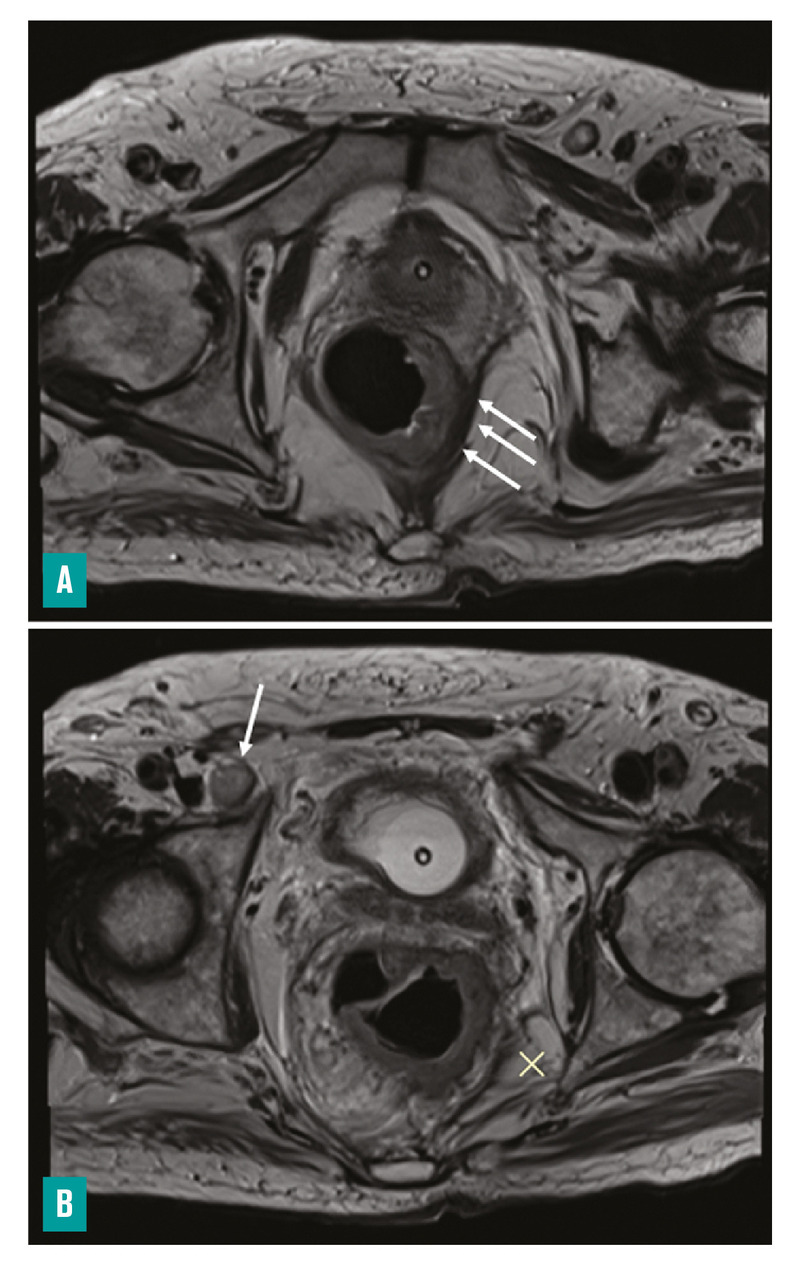

– la distance entre le pôle inférieur de la tumeur et la marge anale et/ou le bord supérieur du sphincter interne (fig. 3 ) ;

– la marge circonférentielle (CRM) : distance la plus courte en millimètres entre le bord externe de la tumeur ou d’une adénopathie, d’un nodule tumoral, d’un embole vasculaire extramural et le fascia recti, ainsi que sa localisation horaire (fig. 3 ) ;

– la distance entre le pôle inférieur de la tumeur et la marge anale et/ou le bord supérieur du sphincter interne (

– la marge circonférentielle (CRM) : distance la plus courte en millimètres entre le bord externe de la tumeur ou d’une adénopathie, d’un nodule tumoral, d’un embole vasculaire extramural et le fascia recti, ainsi que sa localisation horaire (